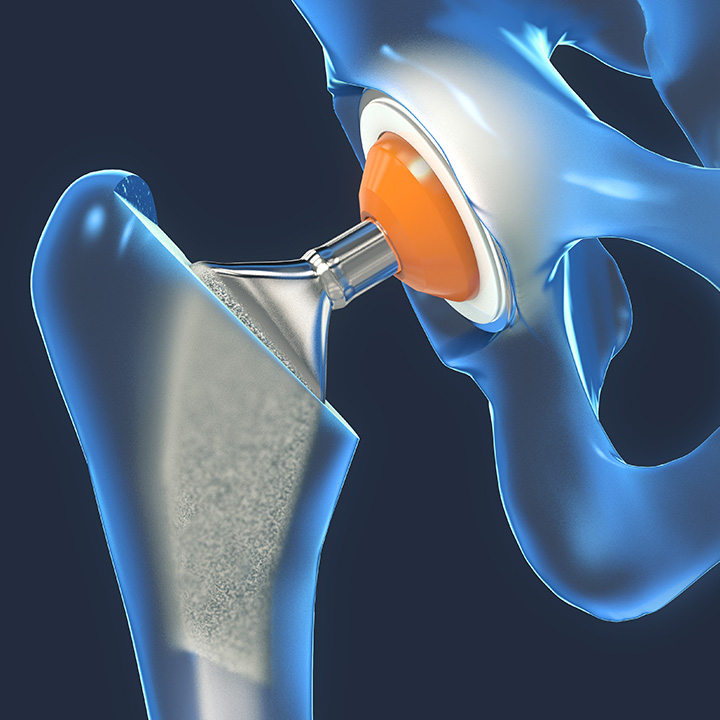

A individualização do cuidado é etapa fundamental do planejamento pré-operatório. No Hospital Moriah, as artroplastias de quadril podem contar com o My Hip Planner®, um sistema que utiliza projeções em 3D para garantir que a prótese seja ajustada e posicionada conforme a anatomia de cada paciente.

Este planejamento detalhado auxilia o cirurgião na execução de uma cirurgia mais precisa, antecipando e evitando possíveis complicações intraoperatórias, como desigualdade de comprimento da perna, instabilidade ou detecção de riscos e falhas no implante.

Um sistema de navegação com tecnologia digital que auxilia os cirurgiões a realizarem com exatidão e precisão a cirurgia de substituição do quadril. Considerada não invasiva, a tecnologia permite que o cirurgião verifique, durante o procedimento, o posicionamento correto para a prótese, reduzindo a probabilidade de deslocamento do quadril e aumentando a estabilidade da articulação.